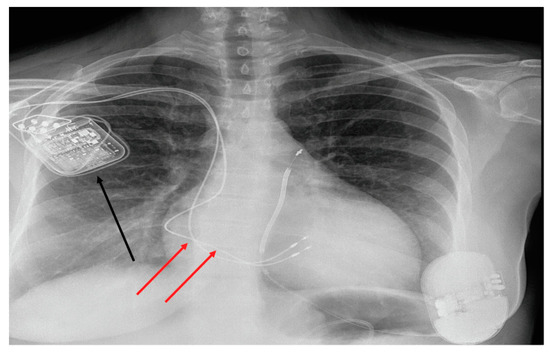

2.2. Optimizer Smart Implant

| ICD-DR (n, %) | 16 (71%) |

| S-ICD | 2 (9%) |

| CRT-D | 3 (14%) |